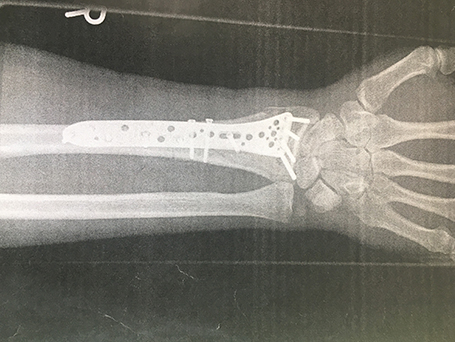

Komplexe rechtsseitige Unterarm-Handgelenksfraktur

Komplexe rechtsseitige Unterarm-Handgelenksfraktur, seitlich